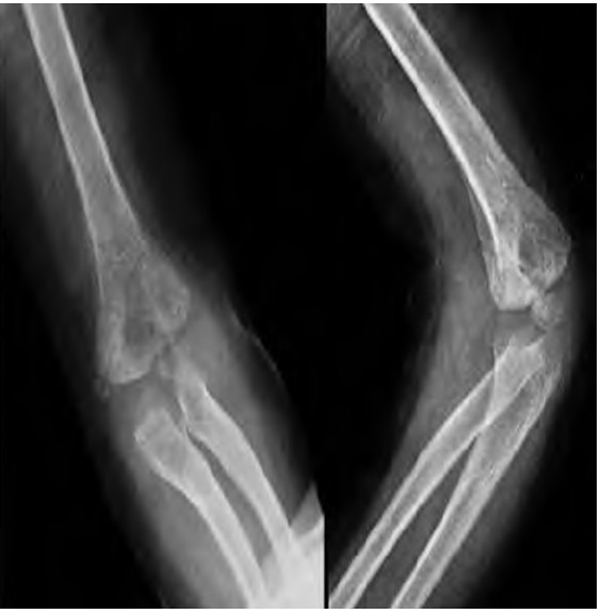

术后予止血、消肿、口服甲钴胺营养神经及抗感染对症治疗,定期创口换药。术后复查DR片提示骨折断端对位对线可,内固定位置良好,桡骨头复位良好,肘关节位置良好(图2)。术后7周拔除克氏针进行功能训练(图3)。术后3个月复查DR片提示骨折断端骨折线已消失,可见较多骨痂影(图4)。随访3年10个月,患儿无肘内、外翻畸形,无肘关节及腕关节活动受限(图5),肘关节 Mackay功能评分为优。

图3 术后7周 DR片示内固定已完整取出,肘关节位置良好